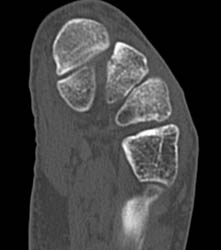

Diagnosis

Collaterals Shown in MPR